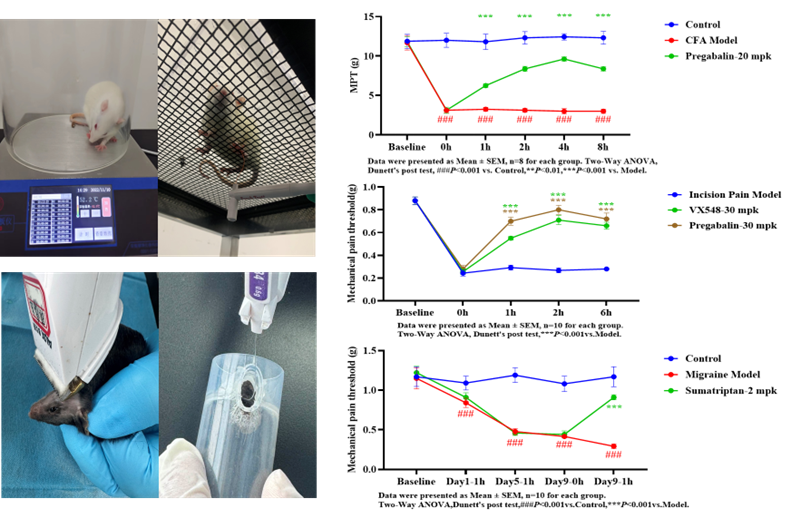

完全弗氏佐剂模型(CFA) |

足底注射CFA |

慢性炎症致痛 |

机械痛阈值 |

术后切口痛 |

足底纵向切口 |

手术创伤→外周+中枢敏化 |

机械痛阈值 |

偏头痛 |

腹腔注射硝酸甘油 |

NO-cGMP→三叉神经血管激活 |

眶周机械痛阈值 |